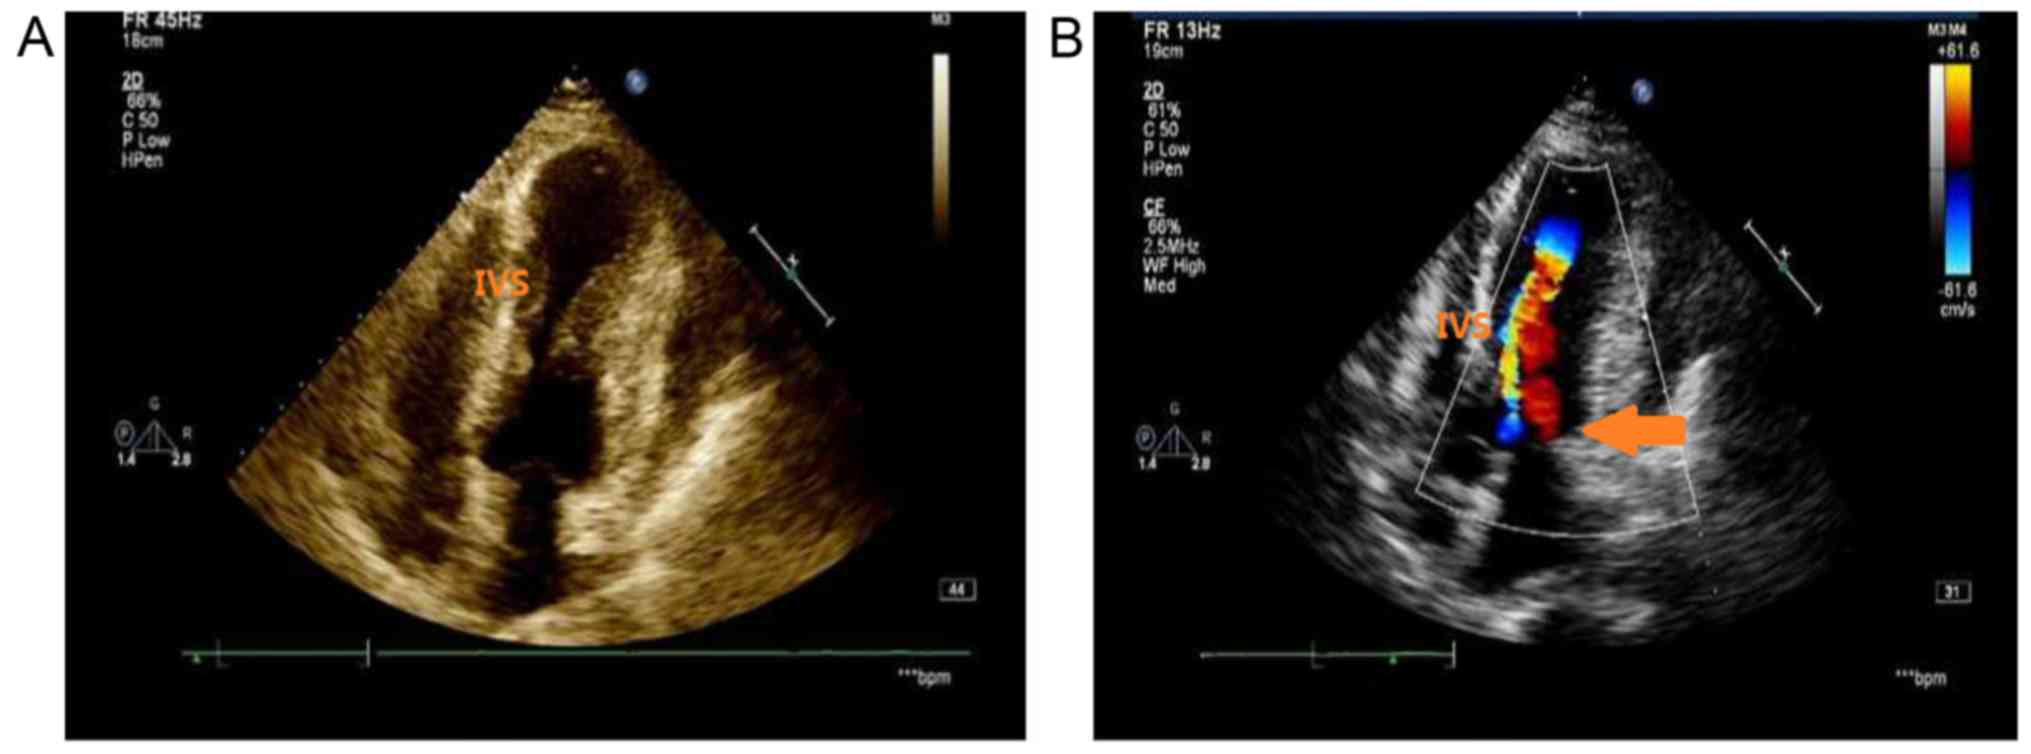

At the 6-month follow-up, the patient had developed dyspnea on exertion (New York Heart Association functional class III (7). Echocardiography indicated marked intracavitary LV obstruction at the mid-ventricular level, with a peak gradient of 80 mmHg. The LV ejection fraction was 45% (Fig. 8).

Figure 8.

Echocardiographic follow-up imaging with four-chamber view on 20th January 2018. (A) The predominant thickening of the mid-ventricular and the formation of left ventricular apical aneurysm. (B) Flow turbulence caused by mid-ventricular obstruction was associated with a gradient of 80 mmHg (arrow). IVS, intraventricular septum.